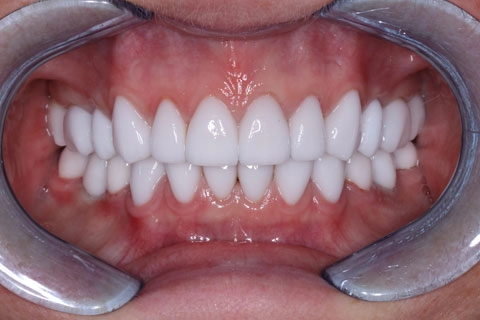

Женщина. 52 года.

Обратилась с жалобами на разрушение зубов 3.6, 4.6, дефекты и дисколорит ранее наложенных пломб. В анамнезе врожденная адентия 1.5, 2.5, 3.5, 4.5

Удалены корни 3.6, 4.6, с одномоментной установкой имплантатов 3.6, 4.6 и забором соединительно-тканного трансплантата с небной поверхности в области 1.6.

Проведена ортопедическая реабилитация.

Фронтальная группа зубов верхней и нижней челюстей – установлены виниры из литий дисиликата.

Жевательная группа – восстановлена коронками из диоксида циркония, в том числе 3.6, 4.6 – коронки на имплантатах.